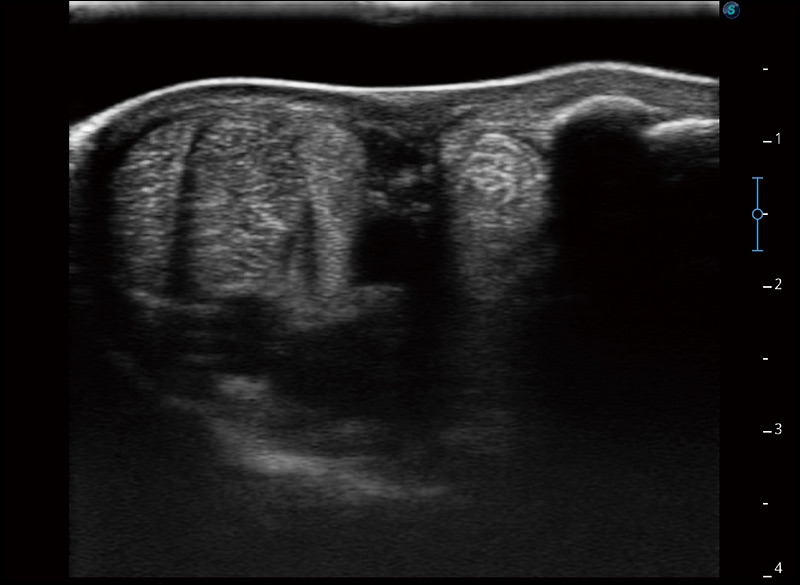

扩展成像

支持线阵和凸阵探头,一键操作即可获得更宽的图像视野

实时宽景成像

可实时观察感兴趣区域和病变位置